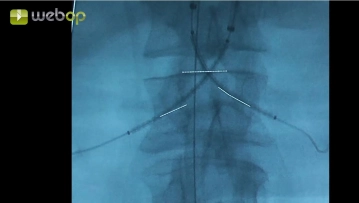

Sondaje de las arterias renales

Ajustes de sonido Nueva punción del conducto en la zona de la arteria subclavia derecha así como avance de otro alambre Terumo® bajo control de intensificador de imagen hasta infradiafragmático e introducción de una vaina 8F así como administración de 2000 UI de heparina. Angiografía con visualización de ambas arterias renales, de la arteria mesentérica superior y del tronco celíaco. Marcado de los orígenes de las arterias renales desde la aorta. Sondaje cuidadoso de la arteria renal izquierda y después de la arteria renal derecha mediante alambre Terumo®. Cambio de los alambres Terumo® a través de catéter Vertebralis por alambres Rosen. Cambio de la vaina femoral izquierda por una vaina 20F y avance de la misma hacia central.